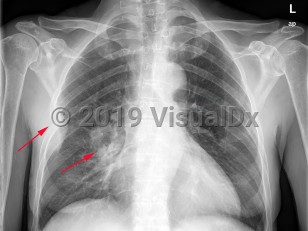

Greater than 95% of lung cancers can be categorized as either small cell lung cancer (SCLC) or non-small cell lung cancer (NSCLC), with adenocarcinoma and squamous cell carcinoma being the most common NSCLC. Carcinoid tumors and mesothelioma may also arise in the lung but are less common. The lungs are also a common site of metastatic cancer.